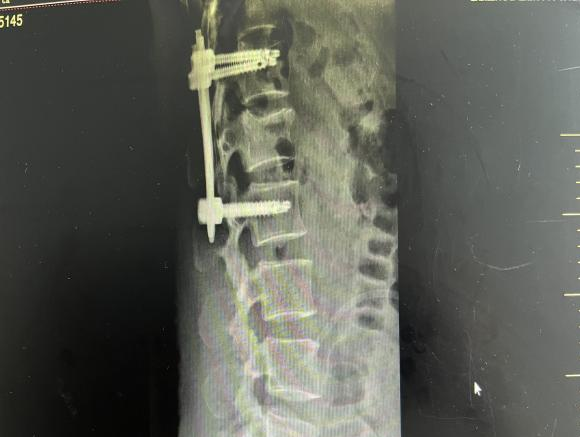

多年来,贵州航天医院各科室紧跟医学前沿,不断强技术、补短板,大力开展新技术、新项目,完成了许多高精尖、高难度、本地区“首例”的技术,填补了医院医疗技术空白,满足了群众日益增长的医疗需求。 贵州航天医院骨科率先在遵义地区开展骨搬移技术,截至目前,已治愈慢性骨髓炎、感染性骨不连、骨缺损、脉管炎、糖尿病足患者200余例,糖尿病足治疗保肢率达到98%。 本期,我们将为大家带来骨科特色技术——骨搬移技术(Ilizarov)。 案例分享 一名59岁的患者,身患糖尿病12年,在来我院3个月前出现了右脚溃烂的症状,来院就诊时,患者的右脚十分红肿,右脚脚趾坏死,伤口处不断流出黑红色脓液,情况十分严重。在接诊到患者时,骨科专家团队高度重视,立刻为患者完善了CT血管造影(CTA)等相关检查,诊断为:2型糖尿病,糖尿病周围血管病变,右糖尿病足。 术 前 考虑到患者情况比较严重,为最大限度保证患者肢体完整,科室专家团队进行了严格的讨论评估,为患者制定了骨搬移技术治疗方案,在征得患者及其家属的同意后,成功通过搬移骨块为患者进行治疗,促进患者病变肢体血管再生。 胫骨横向骨搬移外架固定 清除感染病灶 术后调节外架,通过搬移骨块 促进患肢血管再生 患者在术后三周前来换药,观察到感染得到进一步控制;术后六周复查,患者病变处已愈合,进行CT血管造影(CTA)后可明显观察到足部血管再生。 术后3周 术后6周愈合 CT血管造影见足部血管再生 糖尿病患者全身与局部的问题互为影响,形成恶性循环,糖尿病足溃疡创面迁延不愈,常见干性坏疽、湿性坏疽、趾坏死、深且大的溃疡以及骨髓炎等症状,还可导致脓毒血症,以往为保全生命,患者被迫选择一次或多次截肢。骨搬移技术的发展进步,能在血糖有效控制、局部有效清创下,有效促进患肢微血管再生,改善患肢血供,达到糖尿病足更快治疗康复的目的,并能根据病变情况最大限度的保障患者肢体完整。 什么是骨搬移技术 骨搬移技术是通过使用专用的骨外固定器固定骨段,每天缓慢牵拉,在牵拉搬移过程中,骨段尾部形成新骨及新的软组织,从而修复骨骼缺损及软组织缺损。是治疗大段骨缺损、骨不连、骨感染、肢体畸形的金标准方法,也用于治疗脉管炎、糖尿病足等肢体缺血性疾病。 骨感染缺损 切除感染段 搬移骨段 新骨形成 骨感染根治愈合 骨搬移技术原理 生物组织在持续、稳定、缓慢牵拉下,能刺激细胞分裂、组织再生,骨外固定技术运用该原理,通过持续缓慢调节外固定器形成牵拉张力,促进牵引成骨与相邻组织再生,如神经、血管、肌肉、皮肤等再生,达到治疗大段骨缺损、肢体缺血如糖尿病足等疾病的目的。 骨搬移技术优势 (一)除治疗骨缺损、骨不连外,有更广的适用范围,利用组织再生、血管再生等特性,能大量运用于肢体畸形的矫形、糖尿病足等的治疗。 (二)治疗效果确切,重建肢体外型和功能,极大降低截肢率和残疾率。 (三)明显提高了患者生活质量,极大减轻其家庭及社会负担。 肢体畸形的矫形 慢性骨髓炎 骨段切除 术后1年 濒临截肢的脉管炎术后6周 难愈创面术后3周 贵州航天医院骨科 专家团队 赵学平 骨科主任 主任医师 临床擅长:从事骨科临床工作30余年,对骨科常见疾病的诊治具有丰富的临床经验。 世界中医药联合会脊柱康复专业委员会常务理事,中华中医药学会整脊分会常务委员,中国中西医结合学会骨伤科分会肢体矫形功能重建与康复专家委员会常务委员,中国研究性医院学会骨科创新与转换专业委员会关节外科学组保髋工作委员会常委,中国康复技术转化及发展促进会骨外科与康复技术转化专业委员会常务委员,泛珠三角区域运动医学联盟(PPRD-SMA)理事会常务理事,中国研究型医院学会运动医学专业委员会委员,贵州省中医药学会整脊分会副主任委员,贵州省中西医结合学会银质针专业委员会副主任委员,贵州省康复医学会骨与关节专业委员会常务委员,贵州省人民医院骨科专科联盟常务理事,贵州省康复医学会骨内科专业委员会常务委员,中华医学会贵州省骨科学会委员,贵州省康复医学会脊柱脊髓专业委员会常务委员,贵州省运动医学分会委员,贵州省康复医学会骨与软组织肿瘤专业委员会委员,遵义市医学会创伤分会副主任委员,贵州省康复医学会骨内科专业委员会遵义地区分会常务委员,遵义市医疗事故鉴定、伤残鉴定、工伤鉴定、司法鉴定专家。 长期从事骨科临床研究及教学工作,在国家级、省部级杂志发表论文20余篇,SCI论文2篇,参与主编骨科专著2部,主持省部级科研项目2项,参与指导省部级、市级科研项目6项。 陈明勇 骨科副主任 副主任医师 临床擅长:从事创伤骨科工作约20年,对骨缺损、骨不连、骨肿瘤、肢体畸形等的肢体矫形重建及功能重建,慢性化脓性骨髓炎的根治治疗、糖尿病足的保肢治疗、快速康复理念(ERAS)下的老年骨折的诊治,四肢复杂骨折的诊治,四肢骨折等微创手术治疗具有丰富的临床经验。 2004年毕业于遵义医学院临床专业,曾在中国人民解放军总医院、广西医科大学第一附属医院、上海第六人民医院骨科进修。中国中西医结合学会骨伤科专业委员会横向骨搬移治疗糖尿病足及微血管网再生学组首届委员,遵义市医学会创伤分会常务委员。 瞿 辉 骨科 副主任医师 临床擅长:对骨科的常见病、关节外科、脊柱外科及运动医学疾病的诊治具有丰富的临床经验,熟练掌握骨科手术操作技术。 毕业于遵义医学院临床医学系,2005年前往广州中山大学第一附院骨显微医学部进修学习,2011年前往成都华西医院进修学习,并多次在省内外学习骨科相关知识,是中华医学会骨科分会会员。 赵兴东 骨科 主任医师 临床擅长:擅长骨科的常见病及各种创伤、四肢骨折创伤修复、骨感染、手足疾病的诊治和手足体表畸形的矫形整复,熟练掌握骨科四肢骨病及创伤的手术操作技术,尤其在四肢关节复杂性损伤、手足外伤、组织缺损创面、难治创面的皮瓣修复方面及平足、高弓足矫形方面及四肢慢性疼痛诊治、康复方面具有丰富的临床经验。 硕士研究生,毕业于遵义医学院临床外科系,2015年前往山东省立医院手足外科进修学习;遵义市医学分会创伤分会第一、二届委员,遵义市手外科医学会第二委届员会常务委员;在省级及省级以上期刊发表文章9篇,参编著作2部,参与主持并完成市级课题1项,参与市级课题2项、省级课题1项。 张俊凯 骨科 副主任医师 临床擅长:从事骨科临床工作28年,对创伤骨折、骨感染、骨缺损、骨不连等外科诊治,四肢骨折的微创手术治疗,四肢复杂骨折(如关节内粉碎性骨折、多发骨折等)的损伤控制及手术治疗等具有丰富的临床经验。 1995年毕业于遵义医学院临床专业,2009年前往复旦大学附属医院骨科进修1年。 卢懿明 骨科 副主任医师 临床擅长:从事骨科工作18年,对创伤骨折、四肢骨折的微创手术治疗、四肢复杂骨折(如关节内粉碎性骨折、多发骨折等)的损伤控制及手术治疗,尤其是髋部骨折的PFNA等微创技术,踝关节骨折、膝关节周围骨折的Mipo微创技术等具有丰富的临床经验,开展了4项新技术,发明6项新型专利技术。 2005年毕业于遵义医学院临床专业,2017年,前往南方医科大学第三附属医院骨科进修半年,回院后运用Mipo技术对骨干骨折及干骺端骨折的治疗技术,同时积极开展骨盆骨折、髋臼骨折腹直肌外侧切口的应用;发表了多篇专业论文,经常参与省内外学术交流会授课,获得医院荣誉称号多个。 邬夏荣 骨科 副主任医师 临床擅长:从事骨科工作16年,对四肢复杂骨折、骨肿瘤的诊治,尤其是足踝创伤、慢性踝关节损伤、平足症等诊疗具有丰富的临床经验。 2006年毕业于遵义医科大学临床医学专业,曾在陆军军医大学西南医院进修学习,发表多篇骨科学术论文。 余德怀 骨科 副主任医师 临床擅长:从事骨科工作10余年,对运动医学、骨关节、脊柱外科常见病、多发病的诊治具有丰富的临床经验。 硕士研究生,2011年毕业于遵义医学院临床医学专业,曾前往遵义医科大学附属医院运动医学专业进修学习;是贵州省医学会运动医学分会青年委员,西部关节镜联盟委员;发表多篇骨科学术论文。 冯 乾 骨科 副主任医师 临床擅长:从事骨科工作近20年,熟练掌握骨科多发病及常见病的诊治,尤其对脊柱退变性疾病的诊断及治疗具有丰富的临床经验,主要研究脊柱微创相关治疗方式,能熟练开展椎间孔镜及VBE。 曾前往北京大学第三医院进修学习疼痛及椎间孔镜、首都医科大学友谊医院专业进修脊柱内镜;是贵州省康复医学会第三届脊柱脊髓专业委员会委员;发明专利3项、发表脊柱外科专业论文多篇。 张艳金 骨科 副主任医师 临床擅长:从事骨外科工作16年,对复合伤、多发伤的救治、四肢骨干骨折、关节周围骨折、骨肿瘤、骨髓炎等诊治具有丰富的临床经验。 中共党员,硕士研究生,2006年本科毕业于山西医科大学第二临床医学院,2011年研究生毕业于北京军区总医院;在“老年COPD患者合并髋部骨折的诊治”国际合作课题组研究两年,在老年髋部骨折的诊治方面具有丰富的经验,并发表论文6篇;承担遵义市级课题1项;承担遵义医科大学的临床教学工作,获得遵义医科大学优秀带教老师荣誉。编撰有《骨科疾病诊疗精粹》一书,开展2项新技术,编撰地方规范《务川自治县创伤骨科常见疾病诊疗规范》一书。 赵小锋 骨科 副主任医师 临床擅长:从事骨科临床工作11年,对骨科常见病、多发病诊疗有较为丰富的临床经验,擅长脊柱相关疾病诊断及治疗,尤其是颈、腰、腿疼痛疾病诊断及治疗,擅长胸腰椎骨折微创经皮穿刺内固定术、经皮穿刺椎体成形术、经皮穿刺脊柱内镜下腰椎间盘摘除术、单纯开创腰椎间盘摘除术、腰椎滑脱复位椎间植骨椎融合内固定术、腰椎管狭窄减压融合内固定术及人工髋、膝关节置换术等。 2012年毕业于遵义医学院外科学专业硕士研究生,2019年参加“遵义市115医学人才精英计划”于上海交通大学第一附属医院培训学习,2023年于北京大学第三人民医院脊柱外科进修学习,曾获得遵义市优秀医师荣誉称号。 遵义市手外科第一届委员,遵义市医学会创伤分会第一届委员,遵义市医学会创伤分会第二届委员,贵州省康复医学会第三届脊柱脊髓专业会委员,遵义市医学会烧伤与整形外科学分会委员,发表论文5篇,其中国家级核心期刊1篇,SCI论文1篇,主持市级课题1项并结题,参与市级课题2项。 贵州航天医院骨科简介 基本情况 贵州航天医院(原3417医院)骨科组建于1968年,前身是以创伤和断肢(断指)再植闻名于世的上海市第六人民医院骨科,中国断肢(断指)再植的奠基者、中科院院士陈仲伟等著名专家、学者多次莅临科室指导医疗、教,是贵州省最早拥有专业骨科技术科室之一,在70年代开展了贵州省首例断肢(断指)再植手术。组建50余年来,诊治患者已逾百万,挽救了无数的伤病员,成为了保障遵义地区人民群众健康的重要支撑。 经过几代人的不懈努力,今天的骨科,已由创伤骨科发展至骨病、骨肿瘤、骨结核等领域,现有脊柱外科、关节外科、四肢创伤、手足外科四个亚专科,成为了集医疗、教学、科研于一体的综合学科,是贵州省临床重点专科、遵义市临床重点专科、遵义市骨科临床医学中心、遵义市基层骨科专科联盟理事长单位。 科室目前开放床位110张,共有医护人员50余人,副高级以上专家18人,硕士研究生15人。拥有一流骨科医疗设备多台,每年不定期选派优秀技术骨干到全国各大知名医学院校进修、学习、参观、交流,并邀请国内、国外知名专家教授来院进行交流、指导,通过不断引进国内外先进的诊疗技术,科室医疗技术水平稳步提升,为广大人民群众提供了优质的医疗服务。 专科特色 骨一科 (一)骨缺损、骨不连的肢体与功能重建 胫骨横向骨搬移技术治疗糖尿病足: (二)慢性骨髓炎的根治治疗 (三)肢体缺血性疾病如糖尿病足、脉管炎的保肢治疗 (四)皮瓣修复 (五)复杂创伤的治疗 (六)老年髋部骨折及小儿骨折快速手术 老年髋部骨折: 骨二科 (一)胸腰椎骨折微创经皮椎弓根螺钉固定术 (二)老年性骨质疏松性患者腰椎滑脱脊柱内固定术(骨水泥螺钉) (三)V形双通道脊柱内镜技术(VBE)腰椎融合术治疗腰椎退行性疾病 (四)老年性骨质疏松性骨折(PVP/PKP)术 (五)人工髋关节置换术 (六)双侧股骨头坏死人工全髋关节置换 (七)右侧全髋置换术后假体周围骨折翻修 (八)人工膝关节置换术 (九)人工膝关节假体松动翻修 (十)关节镜技术 传统手术切口 关节镜技术切口 诊疗范围 骨一科 1.四肢创伤、矫形。 2.手、足踝外科。 骨二科